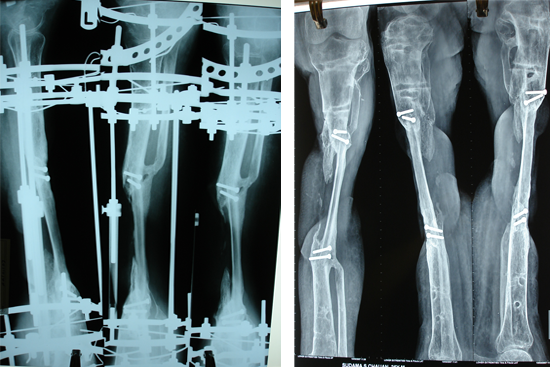

Tibialisation Of Fibula

Shankar Giri

Sudama

Wagh